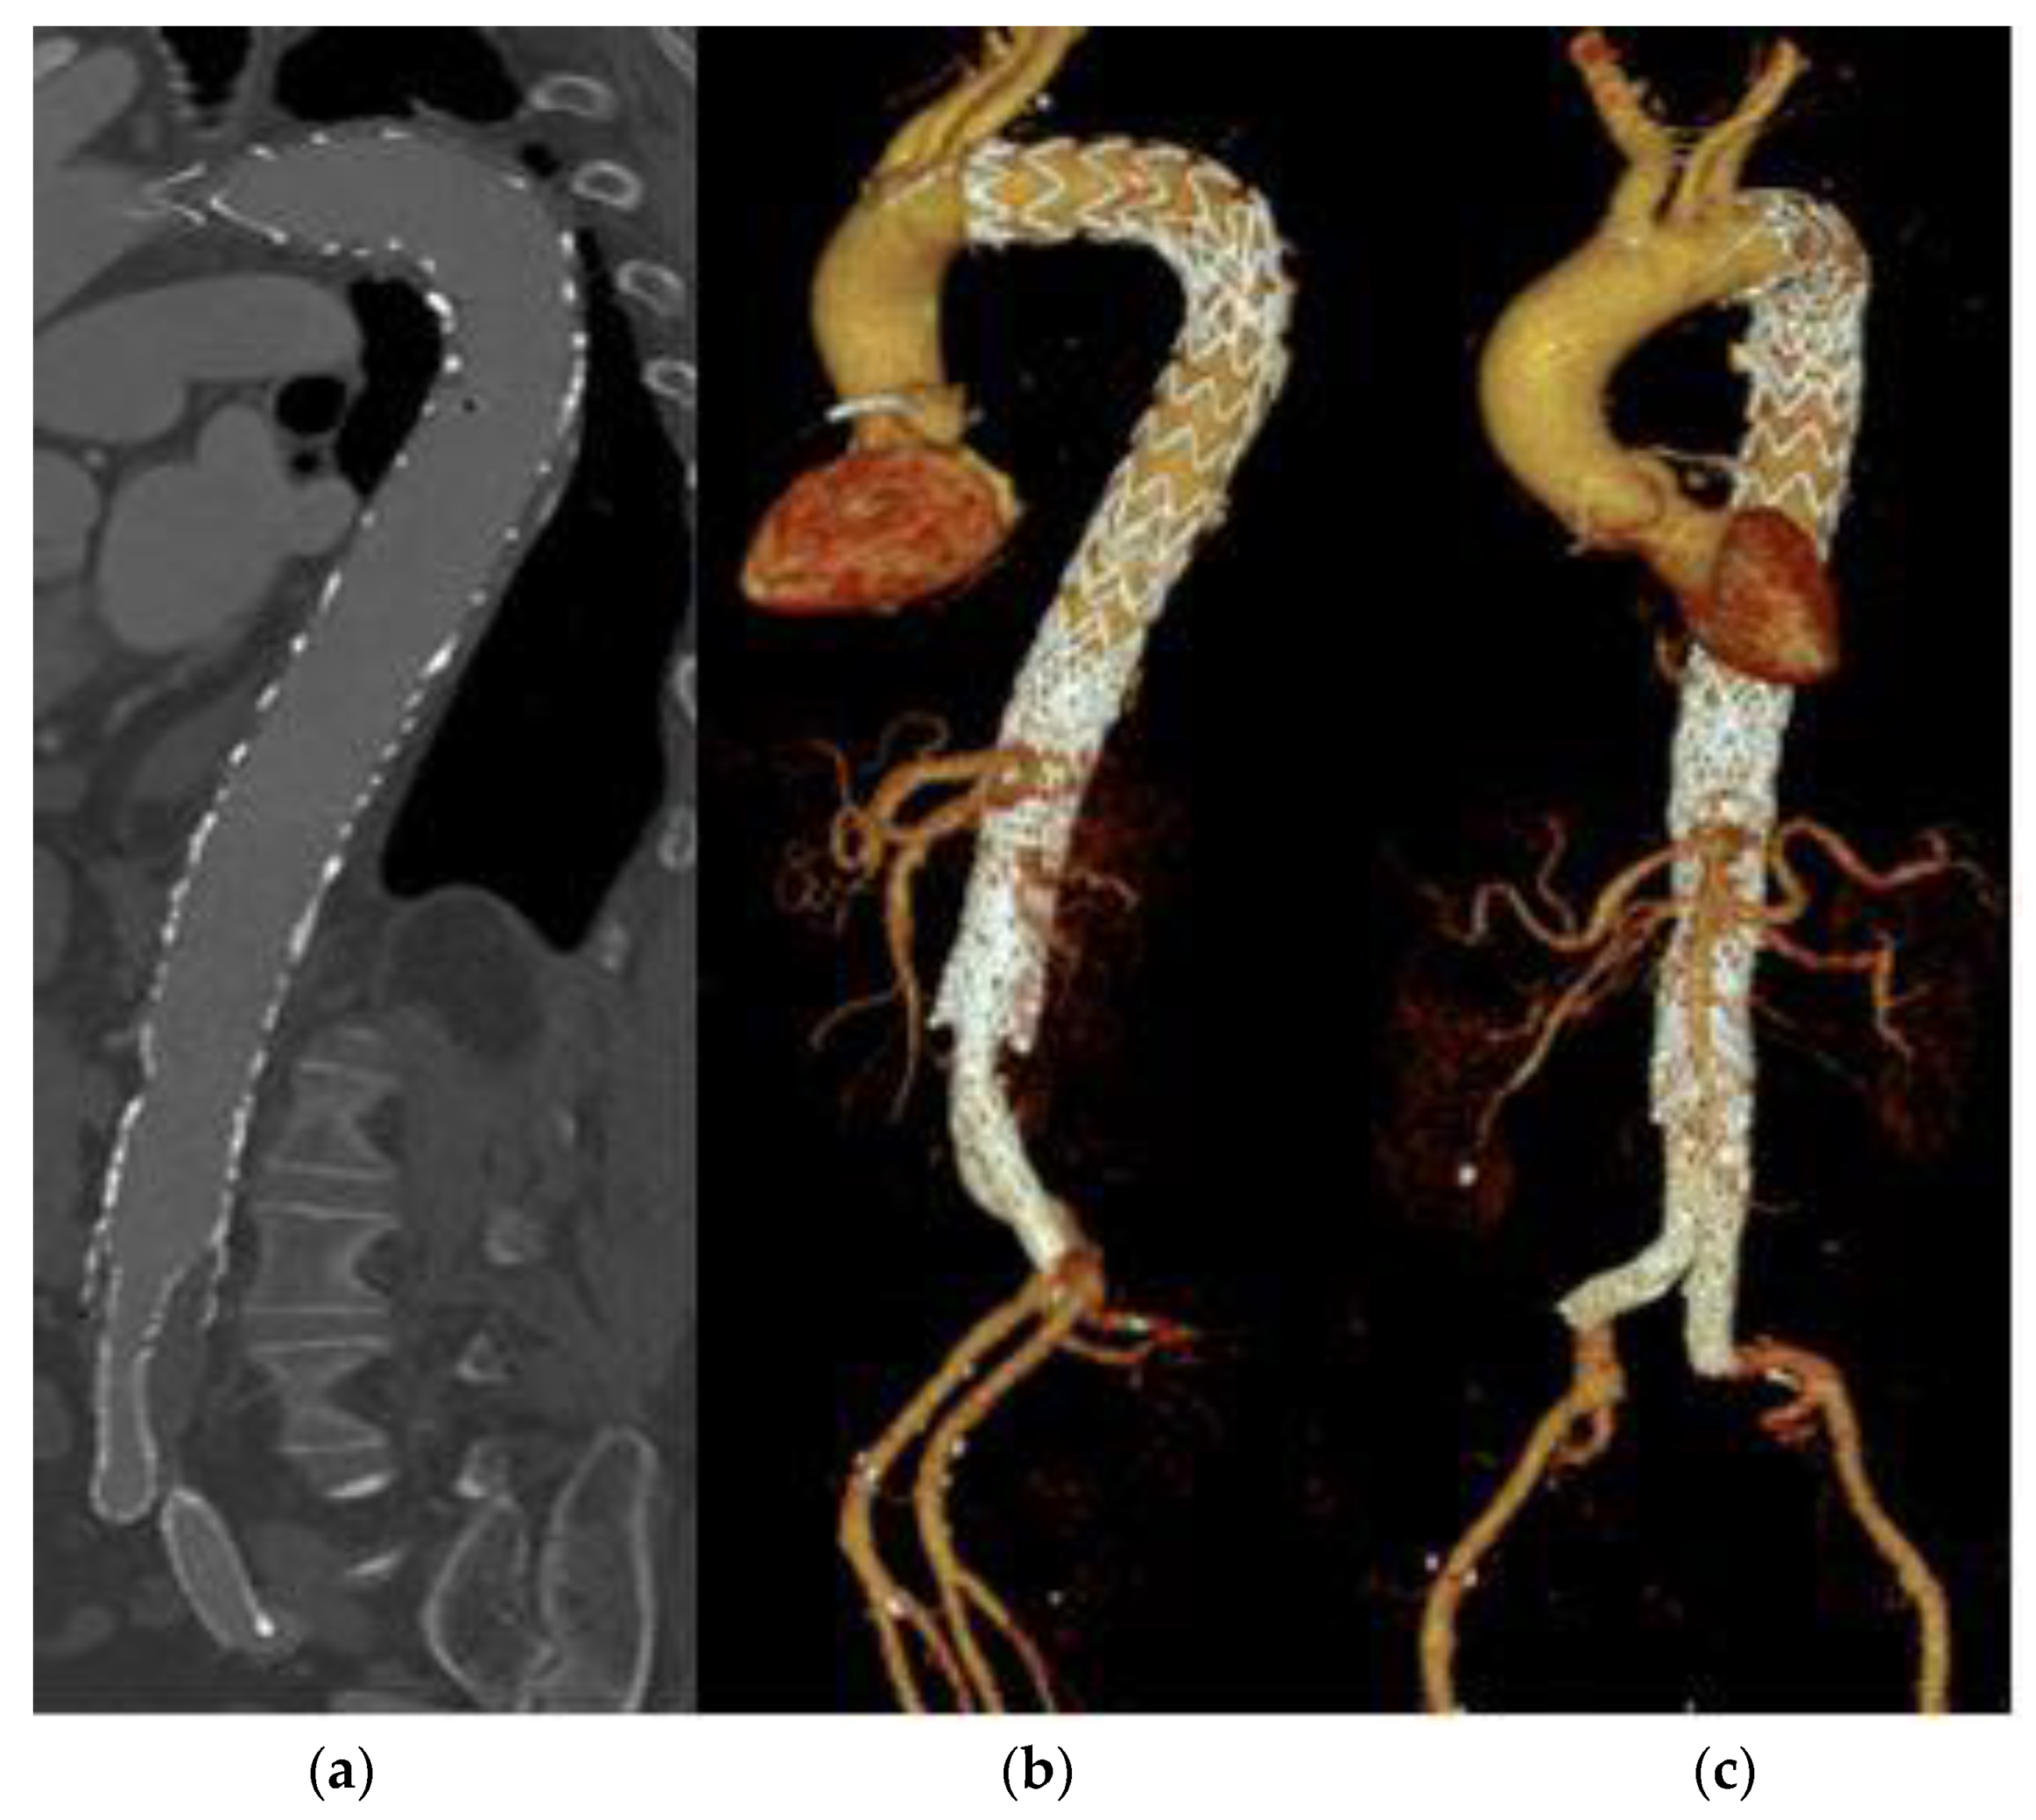

About a third of all patients (n = 49, 36.8%) required a reintervention. The reasons for a reintervention were various, mostly progress of dissection, an endoleak or the development of an aneurysm or pseudoaneurysm. The rarest cause for a re-evaluation of therapy was an insufficiency of sutures after the primary intervention (n = 1, 2.0%), which was only detected in one patient. In average, reintervention was performed after 27.5 months, but there was a wide range with a maximum time interval of 134 months until reintervention. About 15 patients (11.3%) had to undergo a second reintervention. This second reintervention was done after an average of 38 months. Five patients required three or more reinterventions. The maximum number of interventions was five reinterventions, this could be documented for one patient. Figure 2 shows an interventionally treated dissection of the aorta in three different views. On the left, the aorta is shown in a CT from the lateral side. In the middle and on the right, 3D images of the entire aorta are shown from the lateral and ventral views. In the area of the infrarenal aorta, an overlap of the aortic stent and the Y-prosthesis is evident. No endoleak is visible.

Figure 2.

Aortic dissection after stent implantation and Y-prosthesis. (a) CT view from lateral, (b,c) show a 3D visualization of the entire aorta from lateral and ventral view respectively.